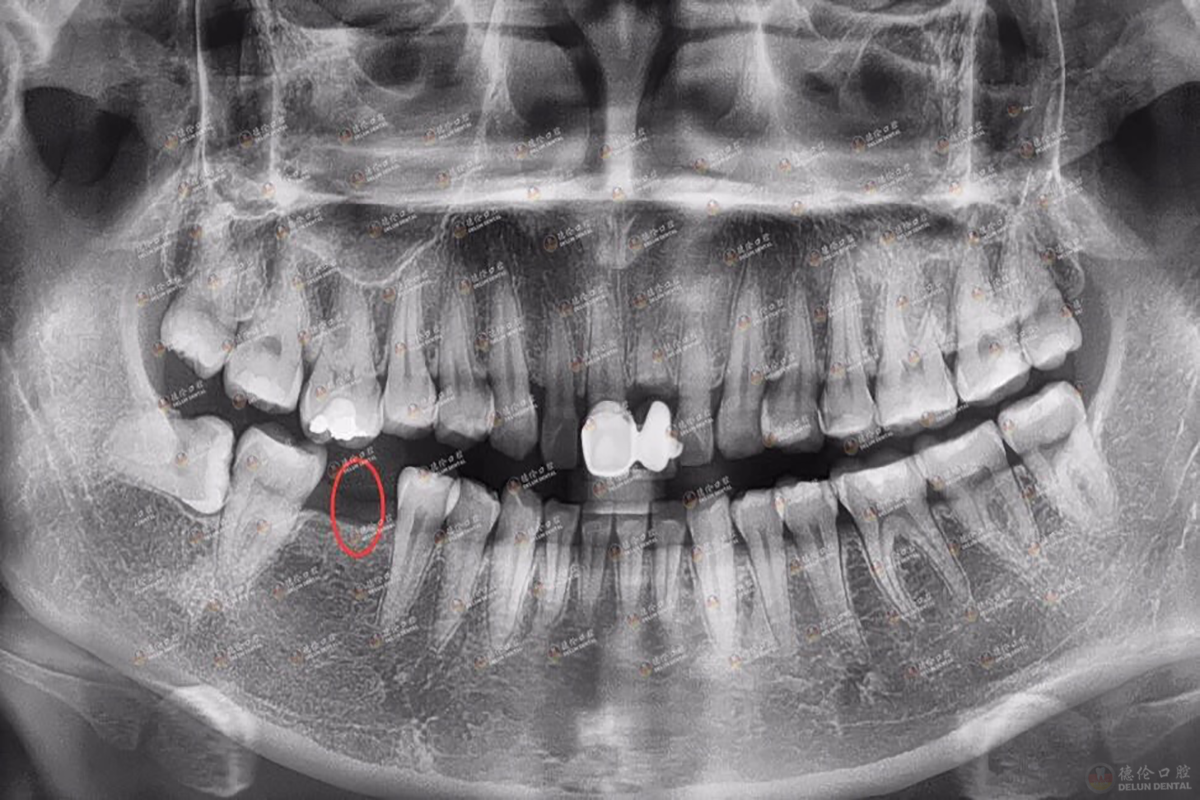

数字化种植牙是利用CBCT和数字化设备进行术前数字化诊断,全面看到患者的口腔信息数据,避开患者血管神经,然后利用3D打印技术,根据患者口腔信息数据,制作出个性化的导板,大大提高手术的准确性,凭借导板的准确定位,之后将种植体植入牙槽内,大大缩短手术时间,实现缺牙者的完美修复。

图为邱女士术前X光片